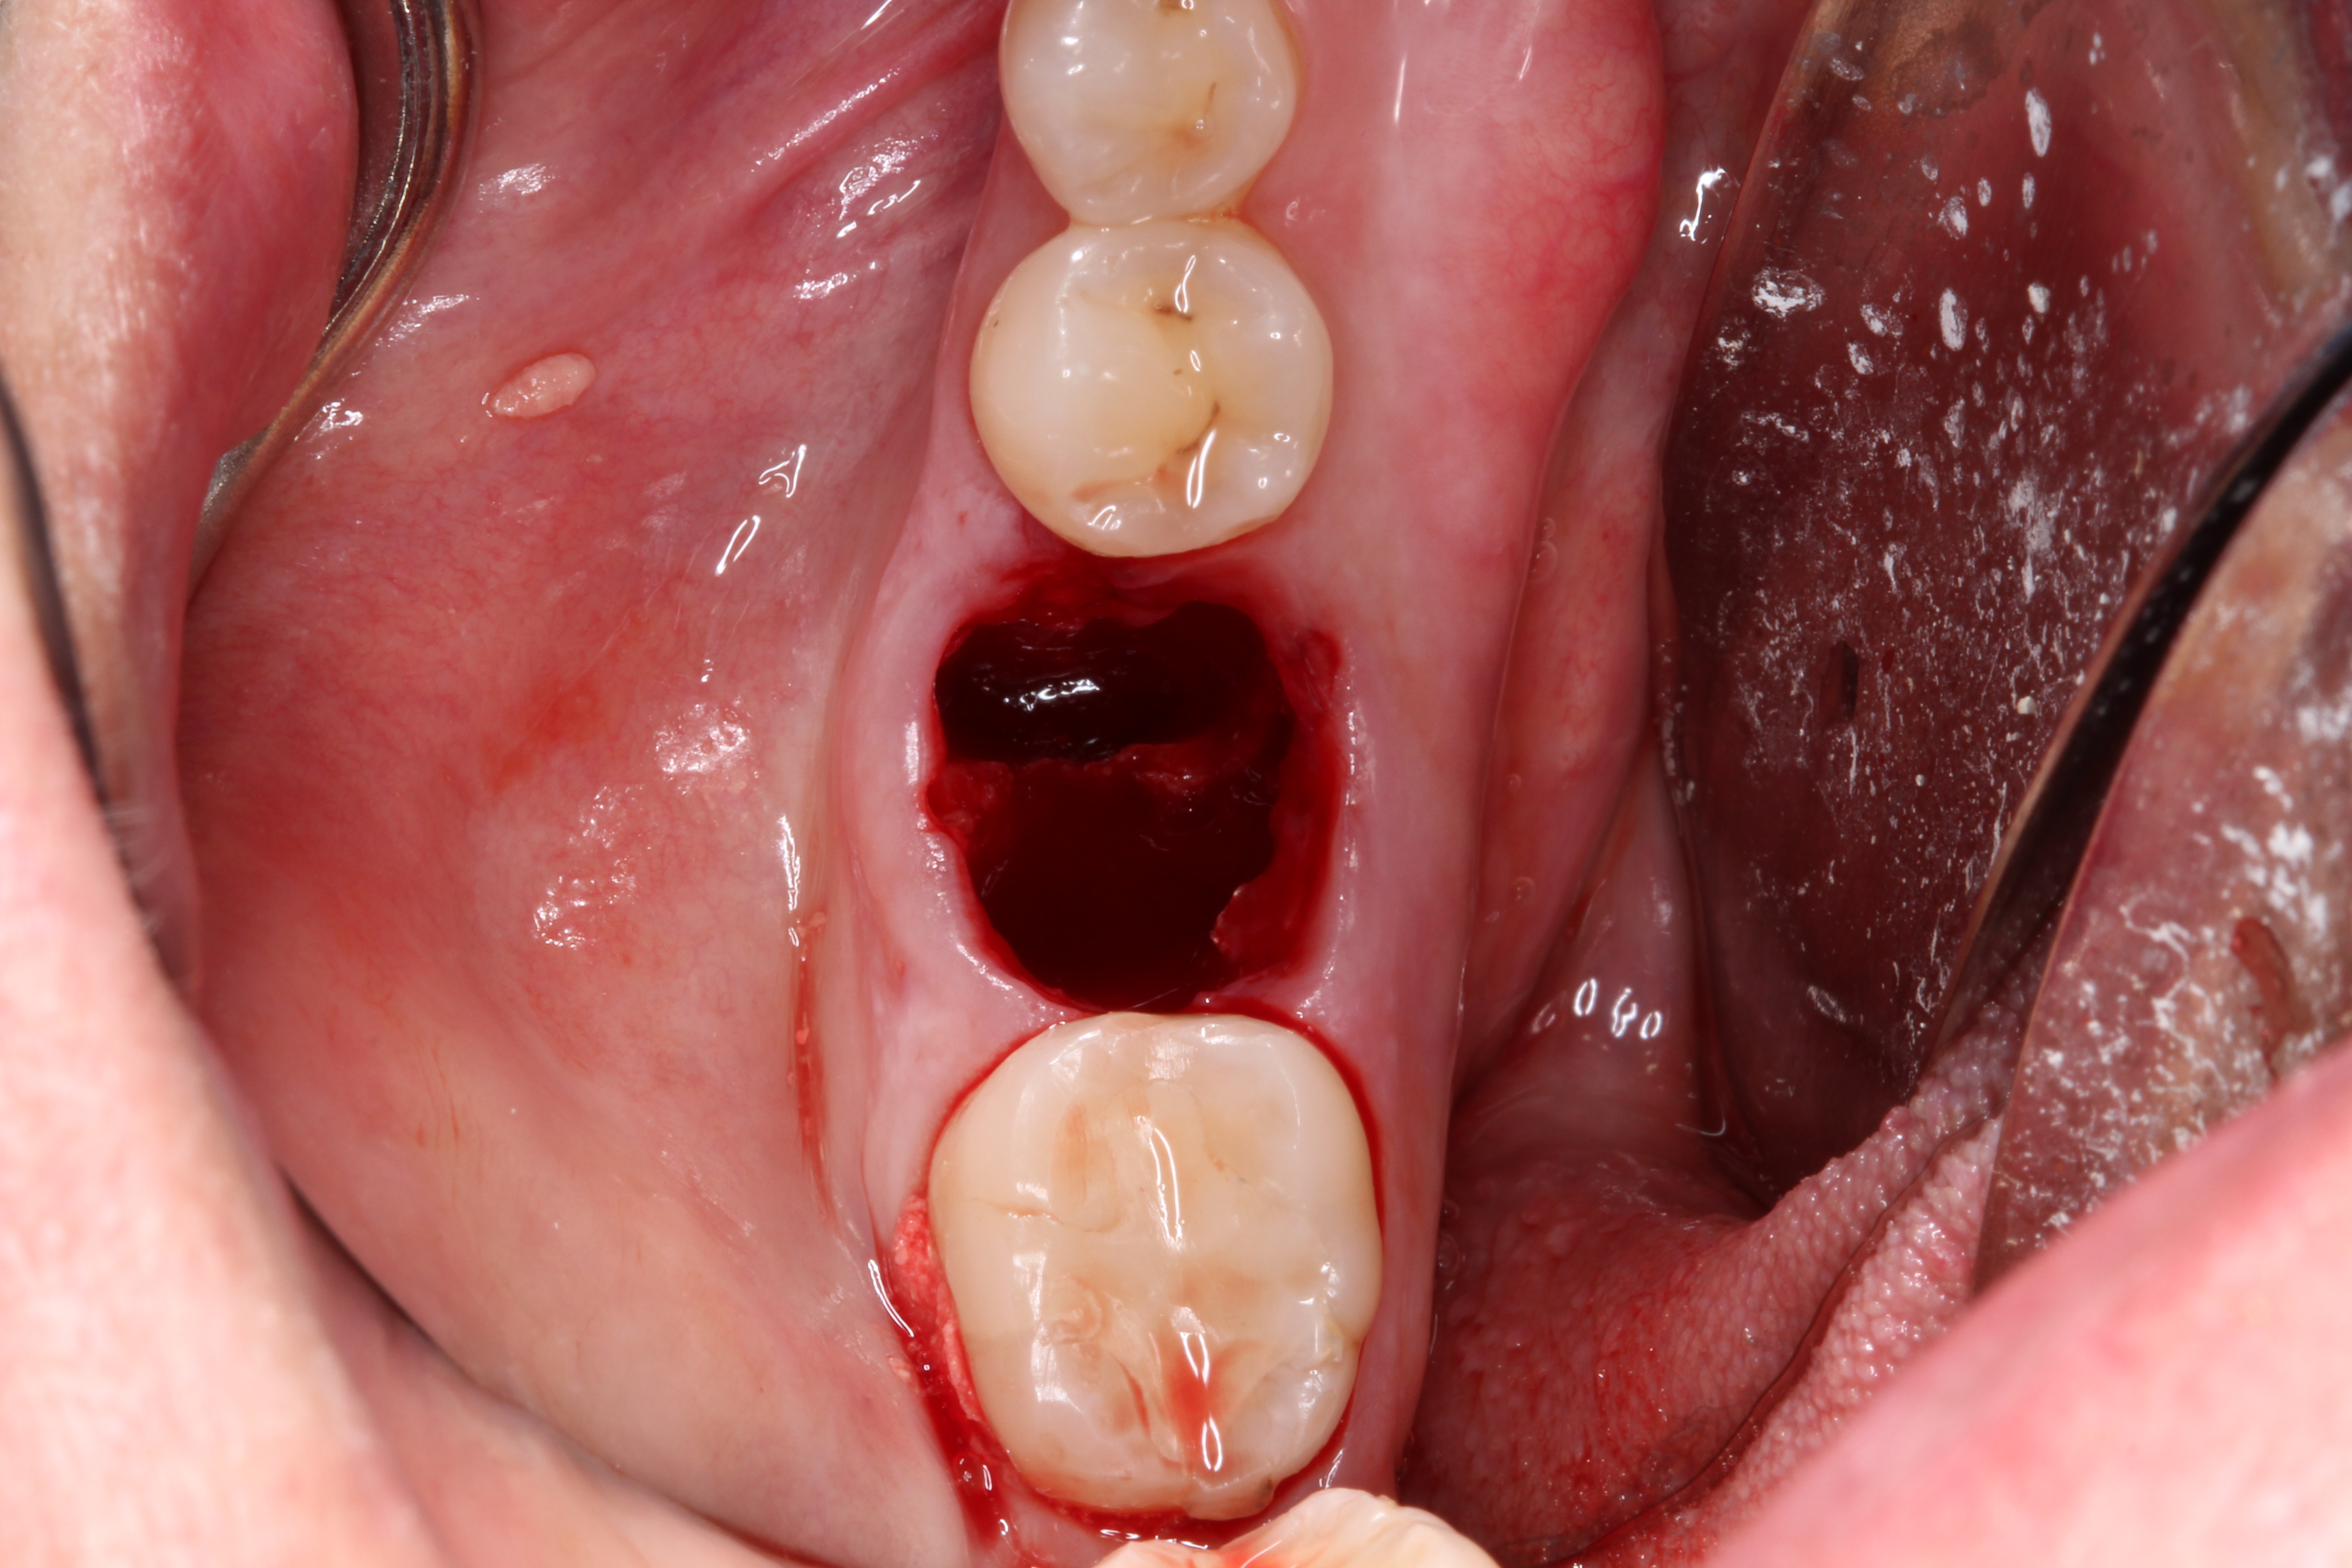

2. The remaining socket should be cleaned and curetted of all remaining granulation tissue or residual soft tissue present at the apex, especially with endodontically treated teeth (Figure 5).

Fig 5. Clean any granulation tissue out of the socket to create a clean wound free of debris.

Figure 5